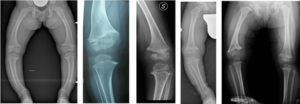

Genu varum is defined as an alteration of the frontal axis of the lower limb that gives it a curved or “parenthetical” appearance (characterized by an increase in the space that separates one knee from the other, unlike genu valgum, which has an “X” appearance). Genu varum can affect only one limb or both.

The axis of the lower limbs of affected patients (it can be just one or both) presents genu varum with a clear deviation of the leg immediately below the knee, associated with torsion of the tibia due to which the tip of the foot deviates inwards. When walking, a sort of yielding of the knee itself towards the outside can be observed (and genu varum becomes even more accentuated).

It is the task of the pediatric orthopedic surgeon to suspect Blount’s disease, distinguishing it on the one hand from the forms of physiological genu varum , and on the other from other forms of secondary genu varum . To this end, radiographic examinations may be performed to search for the typical aspects of the pathology.

The most commonly used synthesis device is the so-called guided growth plate: there are various models that all have the same figure-8 shape. In varus knee , these plates are positioned over the lateral growth cartilage and fixed to the bone using two screws. The surgical incision is limited to 3/4 cm. In the post-operative period, immobilization is not foreseen; from the first day, gradual mobilization of the knee and the start of loading is permitted as tolerated.

To monitor the evolution of the correction, the check-ups use, in addition to clinical measurements, radiographic examinations, both of the knee (to verify that the synthesis devices are positioned correctly) and panoramic (see above) to verify the evolution of the mechanical axis.